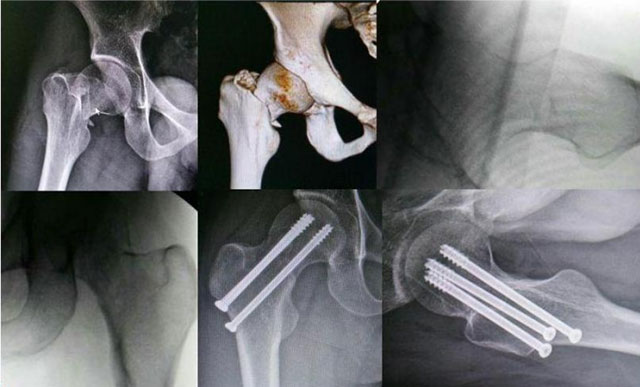

①保守治疗不做手术:股骨颈愈合期为3-6个月,需要长期卧床及制动,小心长期卧床,引发褥疮、肺炎、泌尿系感染等多重并发症,我们的身体是否能够满足条件,目前更多的采取保髋手术治疗。

②骨折不愈合,慢慢诱发股骨头坏死,最终导致残疾。

保守治疗效果不佳最终骨坏死

三枚螺钉固定

动力髋螺钉固定

骨折内固定:可以予以骨折内固定术。如三枚螺钉固定、动力髋螺钉固定。

通俗来讲就是固定两端股骨头和股骨,避免其再次移位,然后慢慢等待骨折愈合。